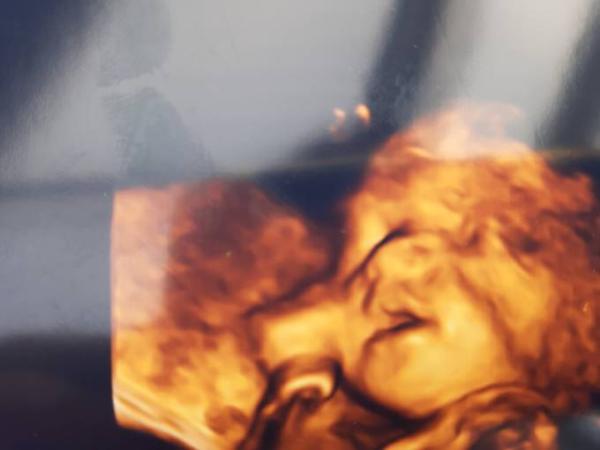

Huhu, bei mir sind es schon vorzeitige Wehen gewesen, die ich hatte. Der Gebärmutterhals hat sich ordentlich verkürzt. War heute zur Kontrolle im Krankenhaus. Alles ok. Die kleine Lady hat sich netterweise mit dem Po nach unten gedreht, wodurch mehr Abstand zwischen Baby und Gebärmutterhals entsteht. Nehme morgens und abends jeweils 800mg Magnesium. Mein Baich wurde komischerweise nie hart, sondern tat immer nur weh. Er hat auch nochmal einen Ultraschall gemacht. Sie hat gerade am Daumen gelutscht Trotzdem bleiben die Bilder gewöhnungsbedürftig

Bild zu